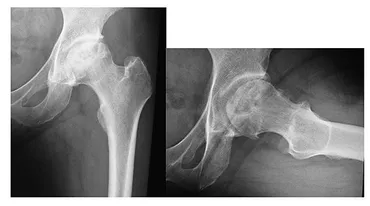

この病気は、大腿骨頭の一部が血流不足により壊死し、股関節の痛みや可動域制限を引き起こします。

✅ 大腿骨頭壊死症は、大腿骨頭への血行障害により股関節の機能に障害が起きる病気で、原因不明の特発性と、外傷などが原因の症候性に分類される。

✅ 症状は股関節痛や動きの制限で、診断には問診と画像検査(X線、MRIなど)が行われる。病期分類や病型分類によって治療法が異なり、保存療法や手術(骨切り術、人工関節置換術)が選択される。

✅ 治療方針は、年齢、症状、病期、病型などを考慮して決定される。壊死範囲が小さい場合は保存療法、大きい場合は手術が検討され、関節温存手術または人工関節置換術が選択肢となる。